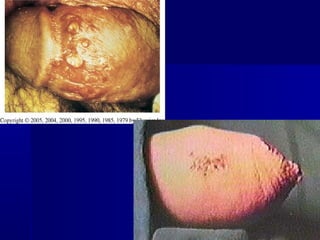

Sífilis I

Cancro duro

Surge cerca de 3 semanas após o contágio. Indolor, de

consistência cartilaginosa, é acompanhado de adenomegalia

regional não supurativa e também indolor.

Cancros fora do alcance da visão podem passar desapercebidos.

Sífilis I                Sífilis & Imunodeficiência

Variante rara, que atualmente

retoma importância com o

advento da AIDS.Clinicamente

caracterizada por lesões

destrutivas, úlcero-necróticas,

fagedênicas.

RIVITTI 1999: 16/17

FOTO JORGE FAGUNDES